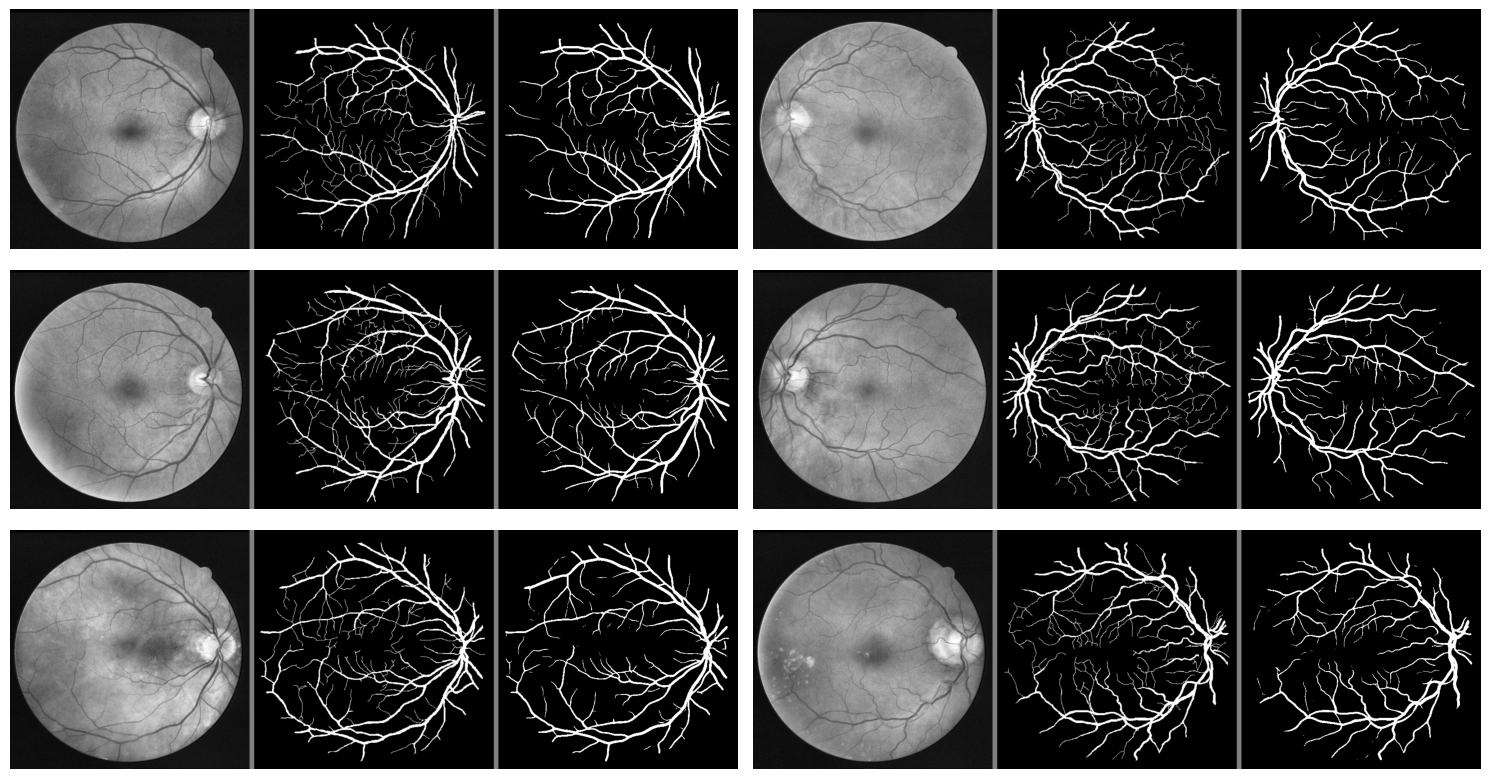

We provide additional samples of predicted masks (Fig. 10) in order to demonstrate overall network efficacy.

However, despite the overall strong performance, the model exhibits limitations in detecting finer and more minute blood vessels. These smaller vessels are often essential for comprehensive retinal health assessments, yet they pose a challenge due to their subtle and less distinct appearance compared to larger vessels. As observed in Figure 10, several thin and intricate vessels are either partially detected or entirely missed. Additionally, predicted vessels sometimes appear thicker than their corresponding true mask counterparts.